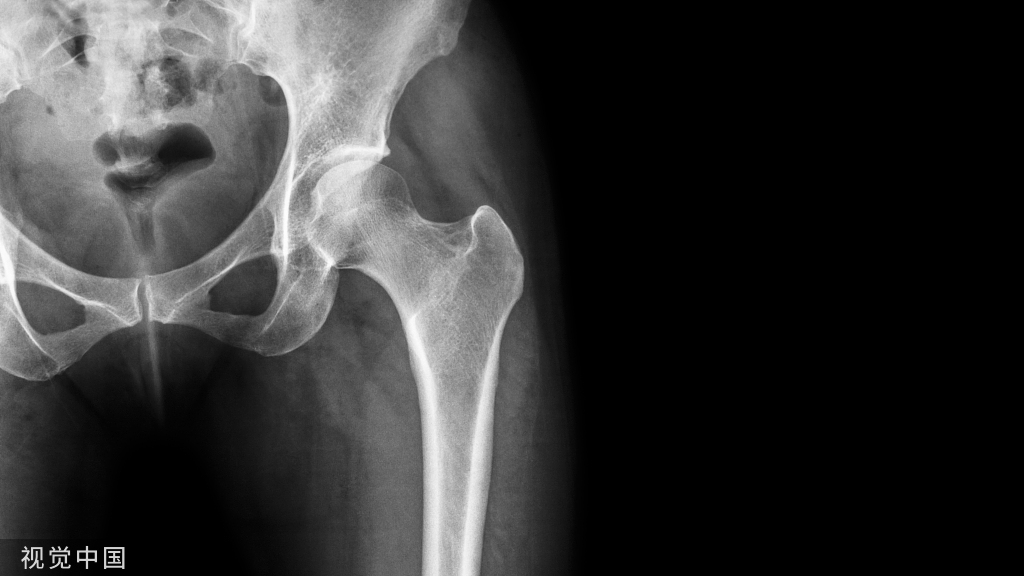

根据数据显示,每年全国近100万例患者需行人工关节置换手术换上人工关节,由它替代人体受损的膝关节、髋关节,来帮助人们正常走路、运动。而近几年,中国的人工关节置换手术量已经超过每年60万台,并且正在以平均每年超过15%-20%的速度递增。这说明了人工关节置换手术在中国的普及程度越来越高,也反映了人们对健康的重视程度不断提高。

为了进一步推动关节外科标准化技术的发展,避免临床上并发症,由德医主办的【人工关节置换规范化手术操作精讲班】于2023年12月23-24日在郑州市召开。

在通过理论授课、新鲜 cadaver 标本演示操作、手术视频讲解、手术直播、互动讨论的教学方式,全流程模拟手术场景,“从体表画线开始、入路解剖、髋臼侧处理、软组织平衡、股骨侧处理、术后功能锻炼指导”,系统、全面的学习髋膝关节置换的“标准化”的解剖入路及手术细节技巧,与会人员对人工关节置换术所遇到的问题、解决办法等问题进行了激烈讨论,孙永强教授和夏亚一教授纷阐述自己观点,分享自己手术经验,把学术推向高潮。